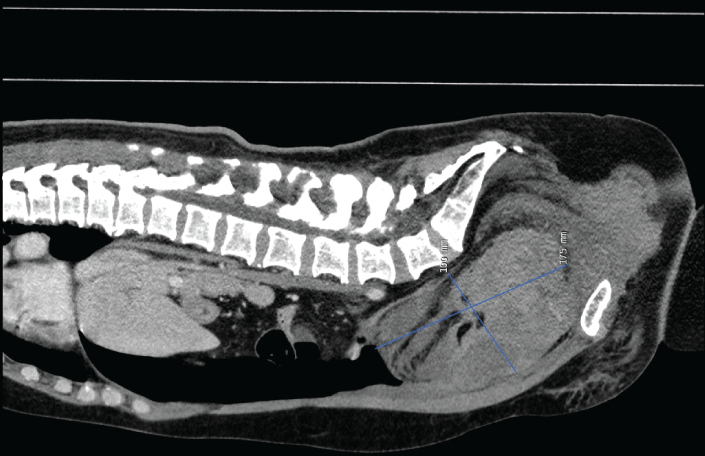

Seven hours after undergoing an uneventful TVT insertion under local anesthesia a 55-year-old non-obese para 2 woman was brought to the emergency department complaining of lower abdominal pain and vertigo. On physical examination, she was alert and aware, but pale, peripherally cold and hypotensive (blood pressure was 80/30 and pulse = 55/minute). Apart from medical treatment for hypertension, she was healthy. Prior surgical history included an appendectomy only. On suspicion of intraperitoneal bleeding, laparoscopic evaluation was performed showing a large hematoma retropubically and on the posterior abdominal wall and after conferral with a vascular surgeon, the decision was made to perform arterial embolization. The subsequent angiography localized significant bleeding from the right obturator artery; an anterior branch of the internal iliac vessel (Figure 1) and a retropubic hematoma 17.5 cm × 10.0 cm in size (Figure 2). The patient was treated by selective embolization with coils of the right obturator artery (Figure 3) and her vital signs remained stable after the procedure. Five days postoperatively, the patients presented with fever of 38.9 ºC and diffuse lower abdominal pain. She received intravenous broad-spectrum antibiotics, the pain abated and an enhanced Computed Tomography (CT) scan revealed a reduced hematoma sized 11 cm × 6 cm. To prevent formation of an abscess and due to ongoing fever (temperature up to 38.9 ºC) laparoscopic evacuation of the hematoma was performed with a total blood loss of 1000 ml on postoperative day 10. Because the upper part of the tape had loosened from the tissue and was visible intraperitoneally, this part had to be removed.

Figure 1: Pelvic arteriography before embolization of the right obturator artery. View Figure 1